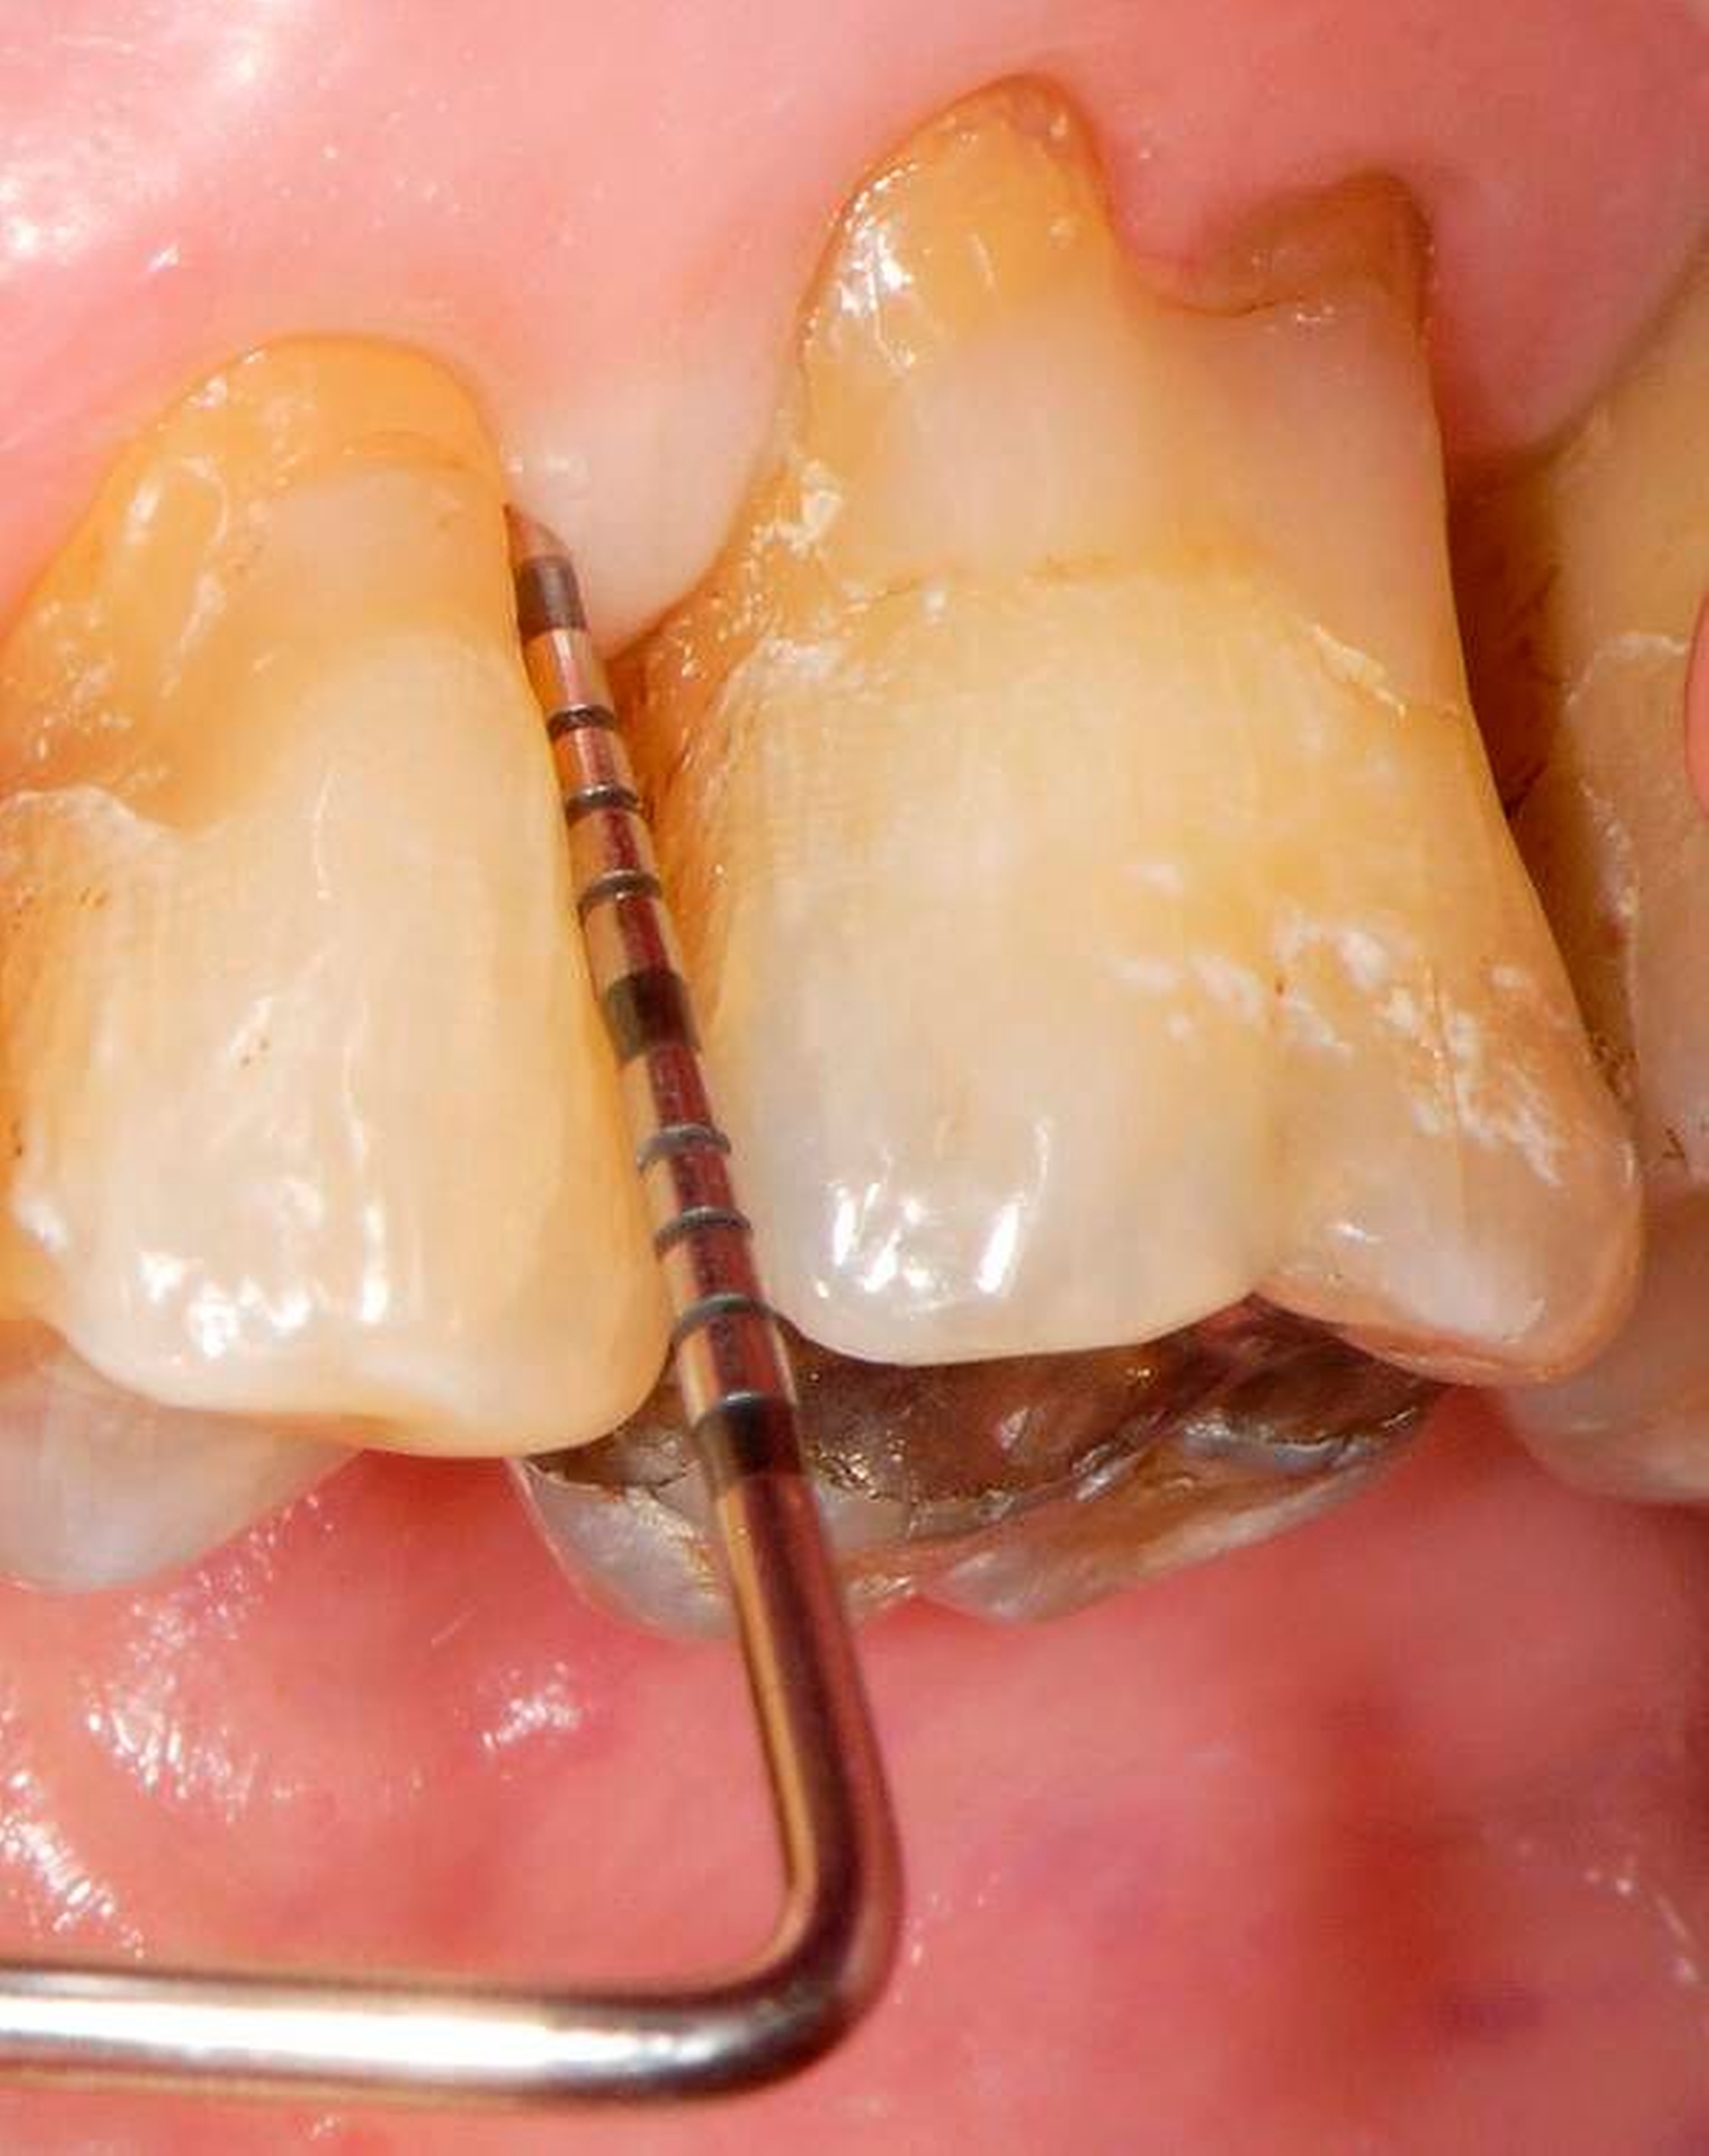

Wenn beispielsweise ein Patient mit tiefen Zahnfleischtaschen Interdentalraumbürsten anwendet, die ohne nennenswerten Widerstand die Zahnzwischenräume passieren, kann man nicht erwarten, dass ihm dies zu einem großen Nutzen für die Zahngesundheit verhilft. Dies betrifft auch Implantatträger [Staehle et al., 2016]. In Abbildung 7 ist ein Patient gezeigt, der trotz Parodontalbehandlung und regelmäßiger Reinigung mit einer – zu dünnen – Interdentalraumbürste hohe Sondierungstiefen und Bluten nach Sondieren aufwies. Erst nach Umstellung auf eine größere Interdentalraumbürste mit längeren Seitenborsten und einem genügend hohen Passagewiderstand durch den Interdentalraum wurde der Taschenfundus mit den Borsten besser erreicht und es kam zu einem deutlichen Entzündungsrückgang.

Eine zahnmedizinisch sinnvolle frugale Intervention für viele Menschen wäre, ihnen eine Handzahnbürste zu empfehlen und dies bedarfsgerecht durch geeignete Interdentalraumbürsten zu ergänzen. Dies wäre in manchen Fällen wesentlich besser, als jemanden durch die alleinige Empfehlung einer elektrischen Hightech-Zahnbürste in einer falschen Sicherheit zu belassen und auf Interdentalraumbürsten zu verzichten. Allerdings muss man einräumen, dass derzeit Interdentalraumbürsten relativ teuer und verschleißanfällig sind und dass das oft sehr unübersichtliche und unvollständige Produktangebot nicht den tatsächlichen Erfordernissen genügt. Insofern besteht hier auch von Herstellerseite Handlungsbedarf.